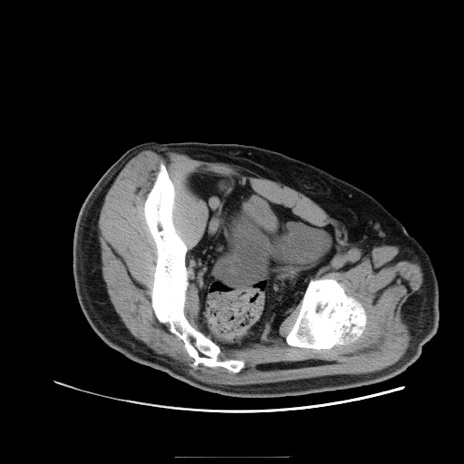

症例22(横断像)

【症例】50歳代男性

【主訴】腹痛

【現病歴】AVMからの被殻出血のため回復期リハ病棟入院中。 本日午後3時頃急に下腹部痛が出現した。

【既往歴】AVM、被殻出血、虫垂炎、高血圧

【身体所見】意識晴明、左半身不全麻痺、会話の理解は良好、36.5°C、腹部:膨隆、全体に板状硬、下腹部正中に圧痛点あり、反跳痛-、筋性防御不明、右下腹部にope scar

【データ】WBC 9400、CRP 0.06